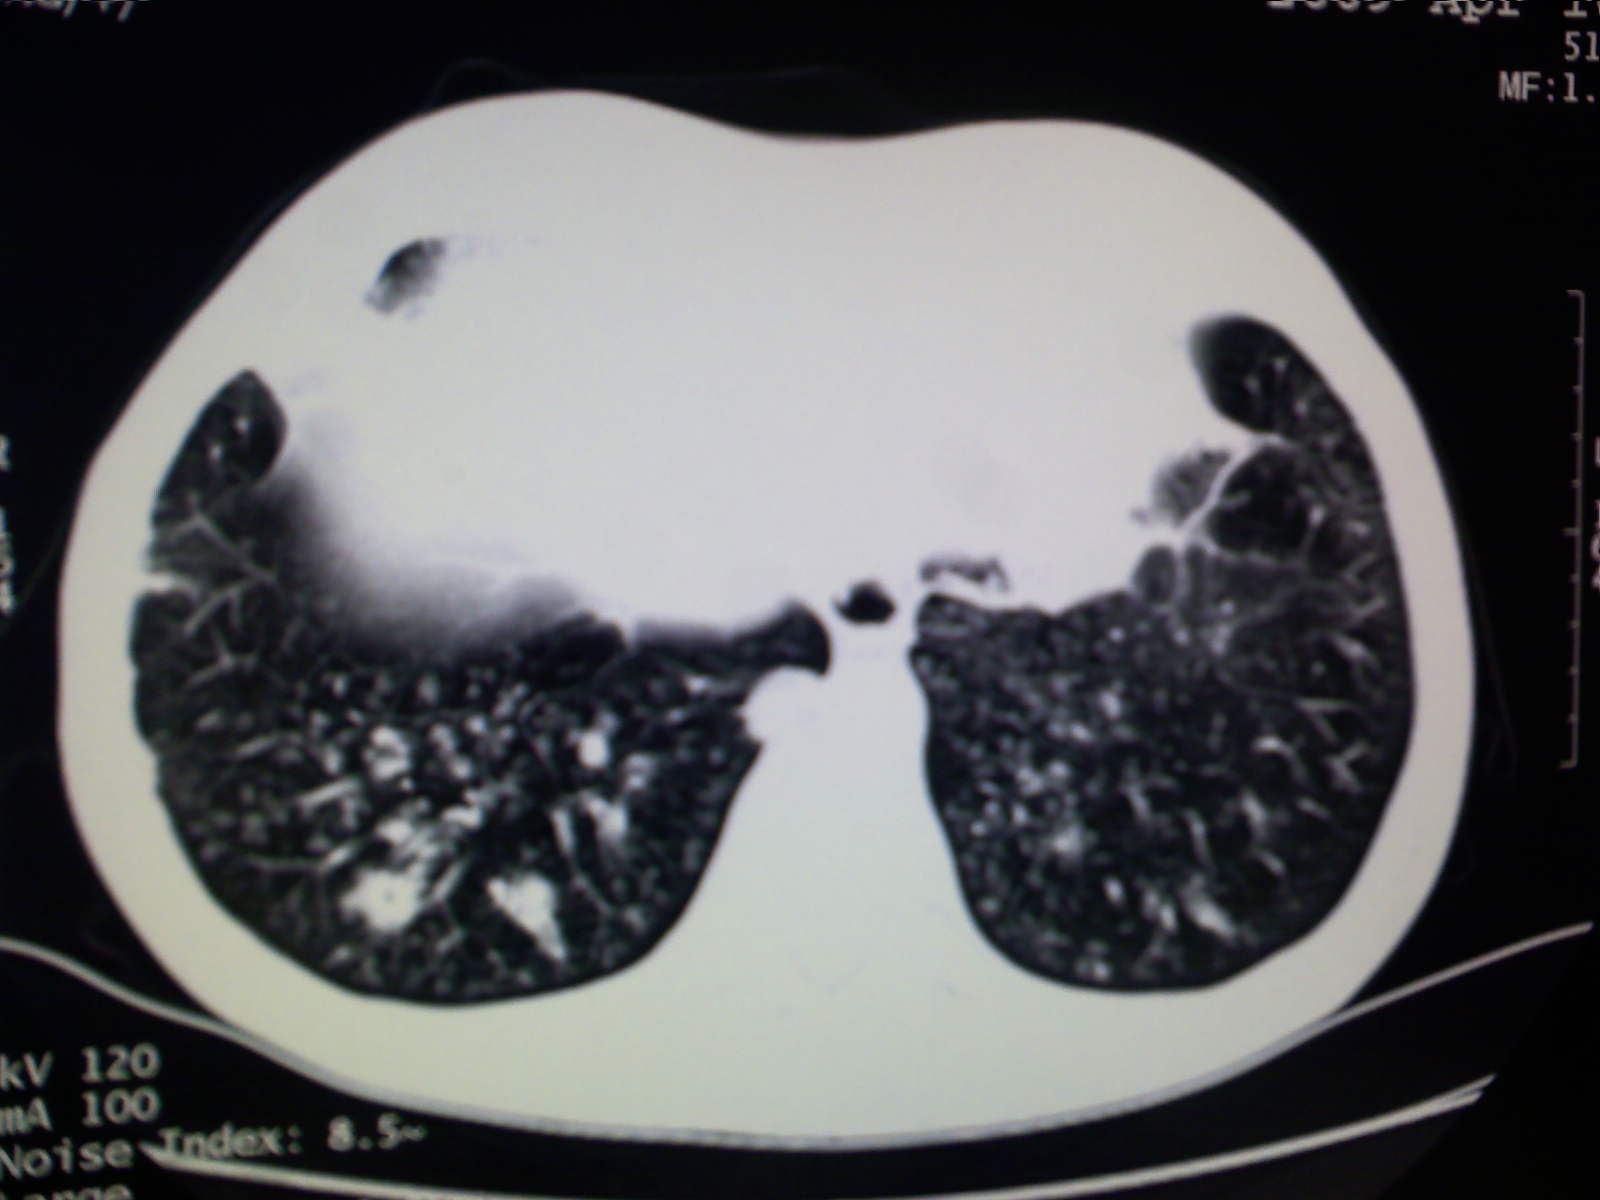

以下是引用卜一在2009-4-11 15:50:00的发言:[br]双肺继发性肺结核伴空洞形成,不排除合并霉菌感染!(病灶呈多形态 多特征 散在分布)。另:合并支气管扩张征伴感染!

以下是引用主力军在2009-4-11 15:55:00的发言:[br]两肺继发性肺结核可能性大。

以下是引用康鹏在2009-4-11 16:30:00的发言:[br]双肺继发性肺结核伴空洞形成合并感染[br]支气管扩张合并感染